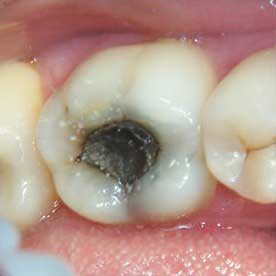

- развитие кариеса, приводящее к образованию «дырок» (кариозных полостей).

Болевые ощущения в верхней части зуба могут быть как ноющими, так и резкими, особенно если в кариозное отверстие попала острая или кислая пища, а также сахар. В случае повреждения эмали стоматолог может не обнаружить кариес, однако пациент может испытывать повышенную чувствительность жевательной поверхности, что вызывает дискомфорт при контакте с холодным, горячим или сладким. После полоскания ротовой полости неприятные ощущения, как правило, исчезают.

- Кариозная полость могла быть недостаточно очищена, что привело к продолжению развития кариеса. В результате зуб начинает болеть, и под пломбой формируется новая кариозная полость.

- Пломба может быть установлена не плотно, что позволяет кариесу продолжать свое разрушительное действие. Это особенно характерно для пломб, сделанных методом химического отверждения. В твердых тканях зуба продолжается разрушение, и боль под пломбой усиливается. Если ситуация не исправляется, болевые ощущения становятся более интенсивными. Когда пациенты начинают ощущать сильную боль, они обращаются к стоматологу, и выясняется, что кариес достиг пульпы, что требует удаления корня. Поэтому, если у вас болит зуб под пломбой, важно как можно скорее посетить стоматолога, сделать рентген и выяснить причину боли.